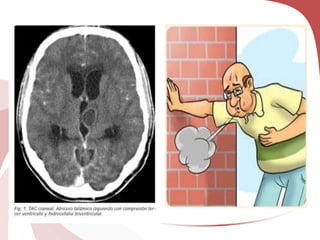

VIDEO